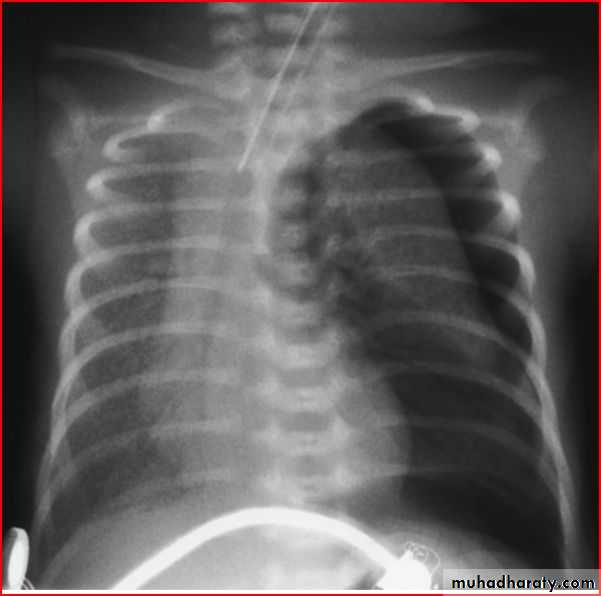

Cardiomegaly

Oligemic lung (devoid vascularty of lung )

Elevation of heart apexRt. Sided aortic notch

BOOT SHAPE HEART ( TOF )